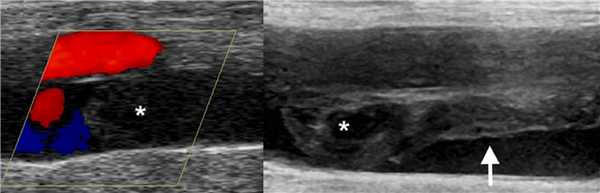

Рис. Правое предсердие умеренно расширенное, в просвете флотирует лентообразный сгусток. Рис. Тромбомасса прикрепилась к межпредсердной перегородке со стороны правого предсердия. Рис. На конце канюли ECMO (стрелка в НПВ) в правое предсердие вошел тромб (правая стрелка).